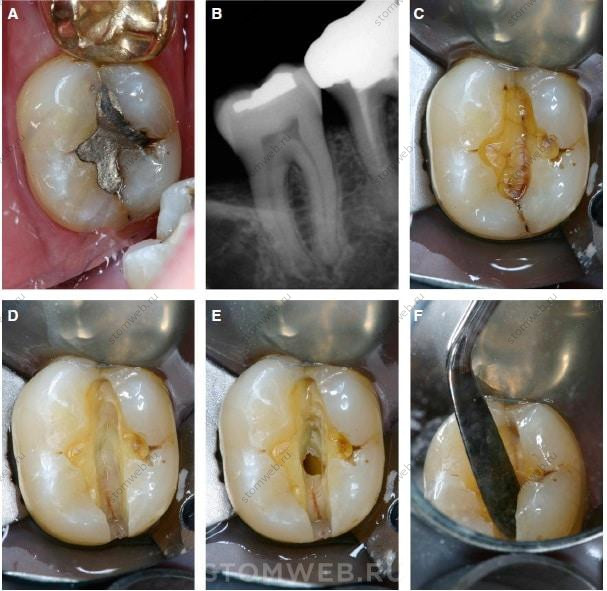

Термин “перелом зуба” означает неполный перелом, который начинается от коронки зуба и распространяется под десну обычно в мезиодистальном направлении. Перелом может проходить через краевые гребни либо по краевым гребням и через боковые поверхности. Перелом либо ограничивается только коронковой частью зуба, либо может распространяться на близлежащий корень (Таблица 1, Рис. 3). Переломы зубов также можно охарактеризовать как неполные (по типу зеленой веточки) переломы, что описывает их форму, или как надлом зуба, такое состояние характеризуется неполным переломом зуба, который частично распространяется через сам зуб. Перелом зуба - вариация перелома бугра, при которой перелом располагается более окклюзионно (Рис. 3 и 10-12).

Рис. 10. Перелом зуба вовлёк медиальный краевой гребень, внутреннюю медиальную проксимальную стенку и частично распространился на дно отпрепарированной полости. Трещина, по всей видимости, не вовлекает дно пульповой камеры.

Рис. 11. (А) Трещины находятся на медиальном краевом гребне первого верхнего моляра, а также на медиальном и дистальном краевых гребнях первого премоляра верхней челюсти. Не обнаружено трещин на втором верхнем премоляре. (В) Трансиллюминация первого премоляра верхней челюсти с оральной стороны показывает, что свет не проходит через линию перелома, создавая то, что называется клиницистами “ночь против дня” и определяет наличие перелома.

Рис. 12. (А) Перелом зуба вовлёк медиальный и дистальный краевые гребни второго моляра нижней челюсти. (В) На рентгенограмме определяется небольшая реставрация, но трещина на ней отсутствует, так как это двухмерное изображение трехмерного объекта. (С) После удаления амальгамной реставрации трещина визуализируется на дне отпрепарированной полости. (D) Удаление дентина вдоль перелома не прекращается (Е) Результат этого - вскрытие пульпы. (F) При действии расклинивающих сил не наблюдается движение фрагментов, что указывает на неполный перелом.

Последствия переломов зуба более серьёзны вследствие их более центрального расположения и более апикального распространения (Таблица 1, Рис. 3).

При поиске перелома важно попробовать визуализировать его длину и местоположение; обычно в этом помогает прямой осмотр в сочетании с окрашиванием и трансиллюминацией. Сначала удаляют реставрации жевательной и проксимальной поверхностей. Затем проводят трансиллюминацию, при которой часто наблюдается характерное резкое преломление проходящего света. С помощью трансиллюминации можно увидеть часть зуба, где возникает просвечивание перелома. В нём находится тонкая воздушная прослойка, которая не просвечивается. Поэтому трещина (или перелом) блокирует или отражает свет, в результате чего выглядит темнее (Рис. 12).

Рис. 13. Перелом зуба в сочетании с переломом бугра. (А) На рентгенограмме определяется обширная амальгамная реставрация, но сам перелом увидеть не удаётся. (В) После удаления части композита визуализируется трещина, вовлекающая дистальный краевой гребень, внутреннюю дистальную проксимальную стенку и распространяющаяся на дно отпрепарированной полости. Также перелом определяется на дне полости, прилегающей к мезиощёчному бугру, распространяясь через оральную борозду. Из-за наличия амальгамной реставрации невозможно визуализировать перелом, который распространяется через медиальный краевой гребень. Также трещина в области щёчной борозды может быть ошибочно принята за другие типы переломов. (С) Удаление дентина для получения идеального эндодонтического доступа позволит получить лучший обзор внутреннего распространения трещины. (D) При действии расклинивающих сил не наблюдается движение фрагментов, что указывает на неполный перелом. (Е) Перелом мезиощёчного бугра лучше визуализируется при осмотре под разными углами. (F) На трансиллюминации отчетливо видна линия перелома.